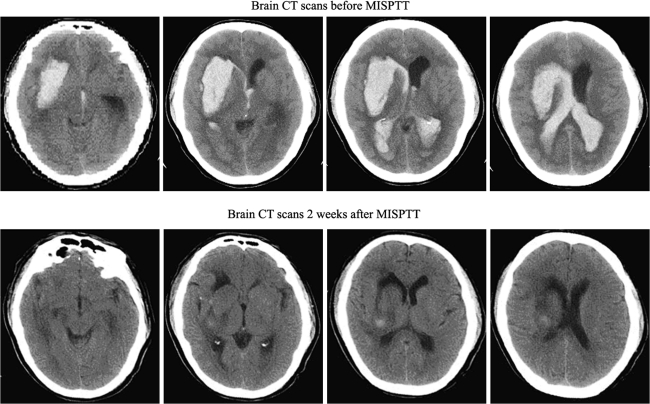

The GCS scores between the two groups prior to the operation were not significantly different (P = 0.998). The total incidence of complication in the MISPTT group was lower than that of the CC group (P = 0.000). Pulmonary infection, digestive tract hemorrhage, and epilepsy in the MISPTT group were all lower than that observed in the CC group (P = 0.047, P = 0.016, and P = 0.010, respectively). The incidence of bleeding recurrence was not significantly different between the two groups (P = 0.199) (Table 2). Typical examples from the study are shown; for example, CT scans of one coma patient (GCS score 5) with a huge hematoma (>70 mL) are shown in Fig. 2. There were obvious difference in the HV and edema of surrounding brain before MISPTT with a GCS score of 5 and 2 weeks after MISPTT with a GCS score of 14. The patient was self-sufficient 1 year after on-set (Fig. 2).

Fig. 2.

CT scans of a patient in a coma (GCS score 5) with a large hematoma (>70 mL) before MISPTT (top), and CT scans of the same patient during consciousness (GCS score 14) 2 weeks after MISPTT (bottom). These scans demonstrate the size of the hematoma on serial axial CT images. CT scans 2 weeks after MISPTT showed obvious amelioration in hematoma volume and edema in the surrounding brain compared with that prior to MISPTT. The patient was able to completely return to a normal lie 1 year after on-set